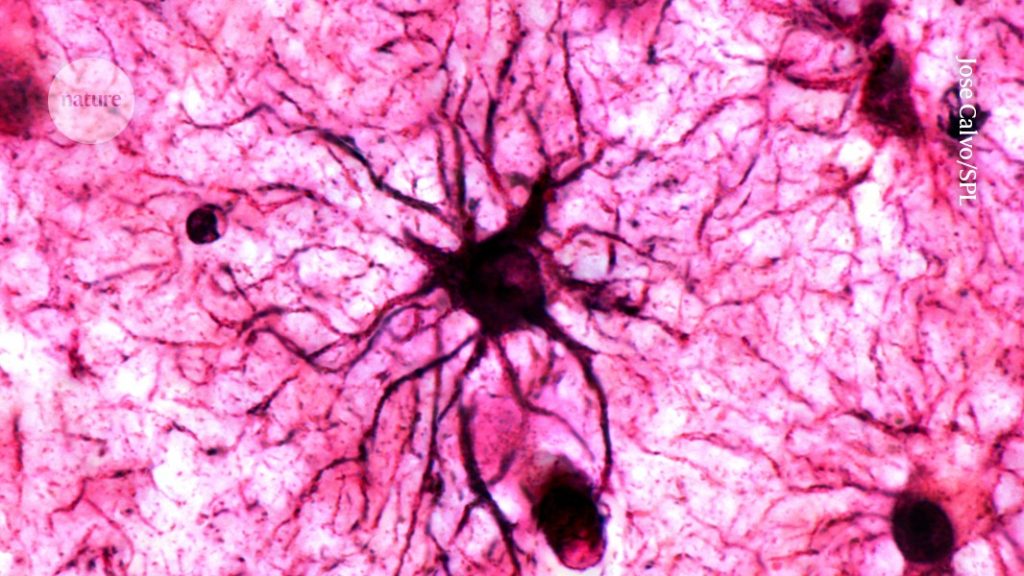

A type of brain cell called astrocytes play a crucial role in stabilizing memories in the brain.Credit: Jose Calvo/SPL Why